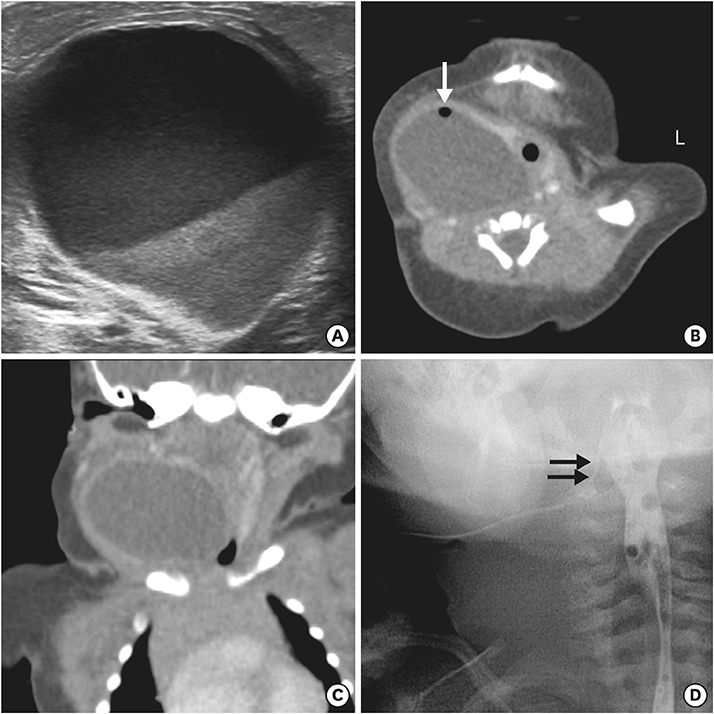

A newborn female infant, gestational age of 39+2 weeks, and 3.46 kg at birth was referred to our NICU due to a 7 cm sized left neck mass presented at birth. No significant medical history during antenatal care was noted. The baby arrived at our NICU 3 hours after birth and physical examination revealed a soft, tense, movable 7 cm long mass without signs of inflammation. Initial neck X-ray showed a 4.7×3.9 cm sized soft tissue density mass at left side of the neck containing round air density (Fig. 3A). With experience of patients with pyriform sinus cysts, gastric tube feeding was initiated from day 1. A sonographic study of the neck mass revealed findings consistent with pyriform sinus cyst, located at the medial side of the left carotid artery and extending to the posterior aspect of the left thyroid gland. The cyst was unilocular and contained isoechogenic debris. Esophagography showed a small tubular opacity from the left pyriform sinus adjacent to the air-filled cyst, suggesting a fistula (Fig. 3B). On neck magnetic resonance imaging (MRI), the fistula was not visualized but a cyst of homogeneous signal intensity without wall thickening or enhancement was visualized with air-fluid level, suggesting communication with the esophagus (Fig. 3C and D). On the 6th day of admission, pyriform sinus cyst resection and fistula ligation was done (Fig. 4). The size of the cyst was 7.0×3.5 cm on operation findings. Histological results of the dissected cyst were negative for malignancy and showed many benign squamous epithelial cells with some multinucleated histiocytes and mixed inflammatory cells. There was no intra-operative complication and the patient recovered uneventfully. Bottle feeding was initiated on postoperative day 7 and the patient was discharged 10 days after surgery.

Fig. 3

(A) Neck anteroposterior view and (C, D) T2-weighted neck magnetic resonance imaging of cystic mass with air (white arrow). (B) Fistulography shows a faintly opacified hairline tract (black arrows) originating from the left pyriform sinus.